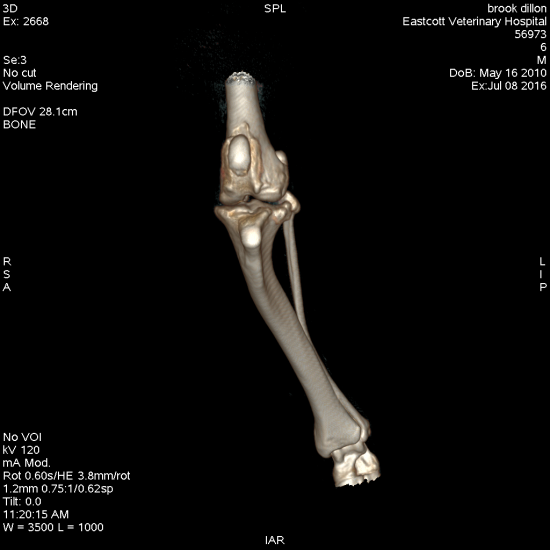

- Concomitant angular limb deformity

- Tibial varus or valgus

All of these can be treated effectively by adapting our standard techniques. For the cases with angular limb deformity including extreme tibial plateau angle (>34 degrees), CT of the hindlimbs allows us to perform an accurate assessment of all aspects of hindlimb alignment. This facilitates planning of the most appropriate surgery, reducing surgical time and leading to excellent clinical results.

Figure 4. Staged bilateral surgical correction of combined distal femoral varus, grade ¾ medial patellar luxation and cranial cruciate ligament rupture using distal femoral ostectomy, block recession trochleoplasty and transposed tibial plateau levelling osteotomy

Figure 5. Treatment of combined excessive tibial plateal angle (56 degrees) and severe tibial valgus deformity using a combined TPLO and cranial and medial closing wedge ostectomies